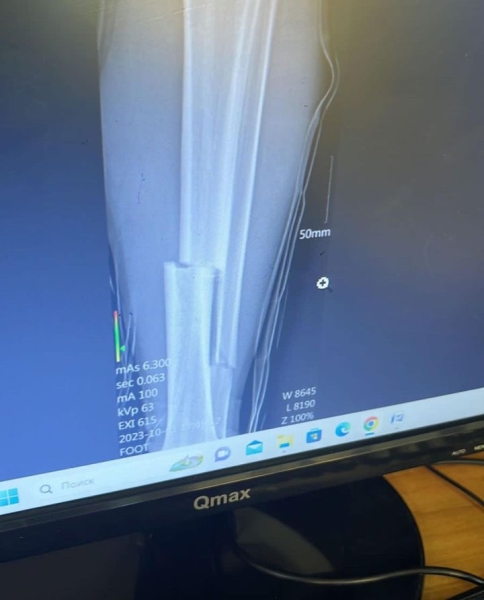

Влетевший в стража ворот форвард "Кайрата" сломал ему ногу в двух местах.

После игры клуб опубликовал в соцсети видео инцидента и снимок с последствиями.

Также "Каспий" проинформировал, что вратарю сделали сложную операцию, после которой его ждет долгое восстановление.